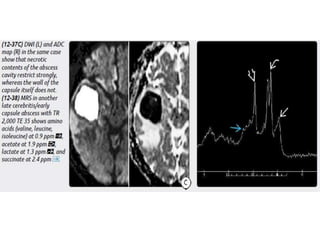

Abscess

Abscess is initiated by focal intracranial infection as an area of cerebritis

and evolves into a collection of pus surrounded by a vascularized

capsule.